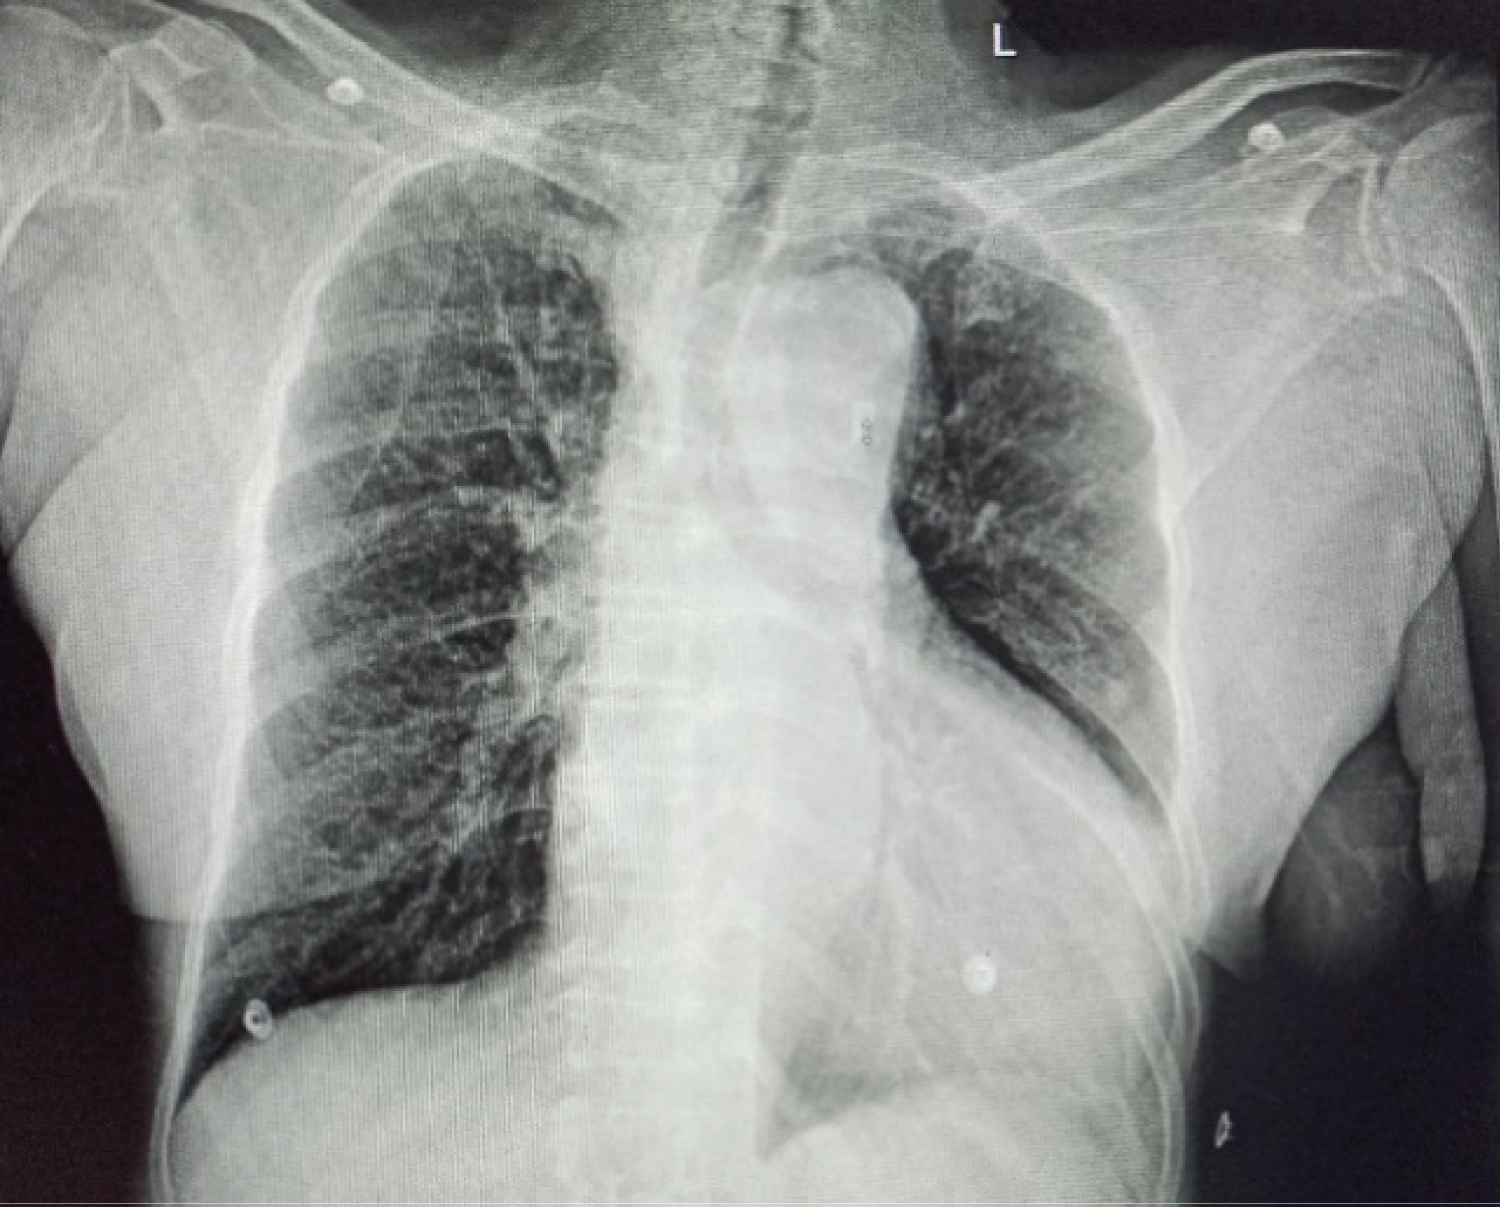

A 68-year-old female patient came to the emergency department with an alleged history of falls at level ground. She was evaluated at another hospital, where an echocardiography finding revealed-a dissection flap in the descending thoracic aorta, moderately severe aortic regurgitation, mildly dilated left ventricle with moderate systolic dysfunction (LVEF-40%), and moderate global hypokinesia. For this above-mentioned echocardiographic finding, she was referred to our hospital. Two years ago, she was diagnosed with dilated cardiomyopathy (DCMP), for which she is taking metoprolol (50 mg) and aldactone. Also, she was known hypertensive for the last 5 years, for which she is taking the tablet losartan (80 mg). Her chest X-ray finding showed cardiomegaly and mediastinal widening (Figure 1), which was consistent with echocardiographic findings and an X-ray of the left hip revealed an inter-trochanteric fracture of the left femur. A CT angiogram (Figure 2) was done, as advised by the cardiothoracic team, which showed type B aortic dissection extending from the distal to left subclavian artery till bifurcation of the aorta and extending into the left common iliac artery with a total aortic diameter of more than 40 mm and patent false lumen of more than 22 mm showing no signs of rupture/impending rupture. Considering her age, and clinical and medical conditions, the cardiothoracic team has advised conservative management for dissection and stratified very high risk for any other surgical procedures. Since the management of an inter-trochanteric fracture is considered urgent and delaying it for more than 48 h increases the risk for both morbidity and mortality, the patient was posted for hip fracture surgery and an aesthesiologists were informed of the same.

Figure 2: CT angiogram transverse section. View Figure 2